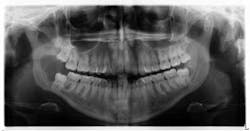

Clinical examination revealed inflamed tissue circa partially erupted No. 32 extending up to the distal of no. 2. The area intraorally was tender to palpation, but unremarkable extraorally. A panoramic X-ray was taken and a large radiolucent lesion was noted to extend from the distal of no. 1 to the distal of no. 32. A significant portion of bone destruction in the mandible was also observed. In addition, a radiolucency was seen distal to the crown on no. 17.

The patient was sent to surgery for enucleation and curettage of the lesion. Differential diagnoses included: unicystic ameloblastoma, odontogenic myxoma, and dentigerous cyst.